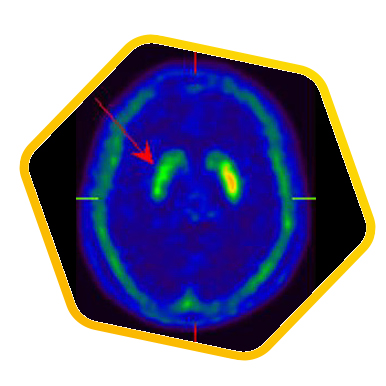

Neurology

![]() [C-11] PIB |

![]() [C-11] Raclopride |

![]() [F-18] DOPA |

PET/CT scans with special tracers can show 3-dimensional images of blood flow and biomolecules deposition in the brain for diagnosis and monitoring the therapy progress of various neurological diseases, such as Alzheimer's, Dementia, Parkinson's disease, Huntingdon's chorea and autism. In 2018, the National Institute on Aging-Alzheimer's Association (NIA-AA) had revised the definition of Alzheimer's Disease (AD) from a syndrome diagnosed by a set of clinical criteria to a biological construct using abnormal protein deposits to define AD as a unique neurodegenerative disease that can lead to dementia. Our hospital has almost 20 years of experience in producing specific tracer to detect abnormal protein deposition in the brain.

- Epilepsy

For some types of epilepsy patients, PET/CT scans can localize the epilepsy-causing focus in the brain. Modern stereotaxic neurosurgery can then cure epilepsy permanently by excising the focus.